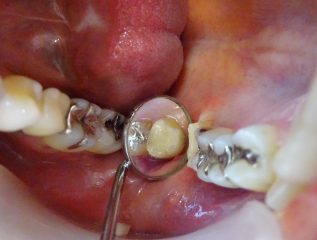

しかし、セレックを使用することで短時間で詰め物が装着でき、虫歯を除去した部分の再感染リスクが軽減できます。

口腔内スキャナーで歯の形を3Dデータ化する「光学印象」で型取りを行い、セレックを使用してセラミックインレーを作製します。今までの型取りなどでは起こりえた歪みが少なく適合がとても良いです。さらに汚れもつきにくいため、虫歯の予防にも効果的です。

そして、セレックの一番のメリットは当日にセラミックのセットまで終わるという事です。